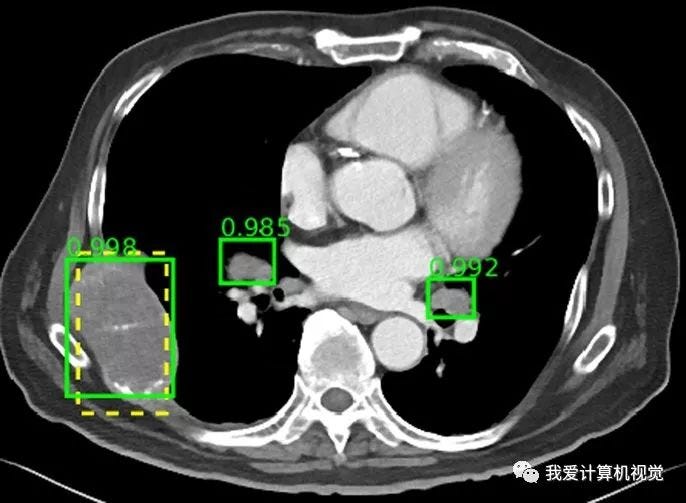

5. Medical Imaging:

YOLOv8 can aid in the automatic detection of anomalies in medical images, assisting healthcare professionals in diagnosing diseases more accurately.